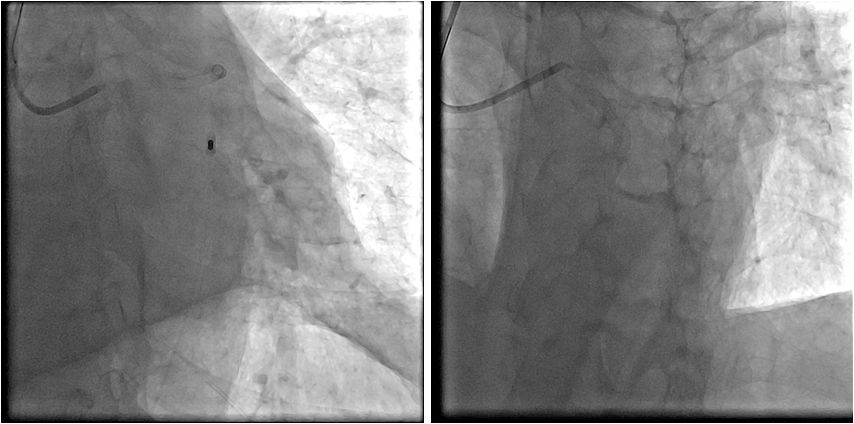

左冠植入支架

支架植入后

PCI术后

➤ 患者术程比较顺利,胸痛症状明显缓解

➤ 但术中使用多巴胺及IABP辅助下,血压始终在80/50mmHg左右,氧饱和度维持在95-99%

➤ 返回病房后,持续使用IABP辅助,大剂量的多巴胺及去甲肾上腺素联合使用,但是血压始终不能回升,患者精神欠佳,意识模糊,血气分析氧分压明显降低,与家属沟通后决定使用ECMO